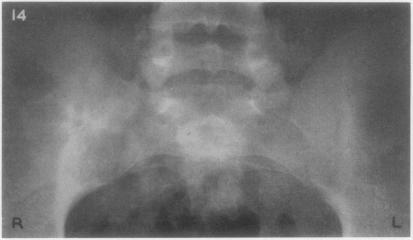

Sacro-ilitis in Still's disease.

Ann Rheum Dis. 1962 Jun;21(2):105-20. doi: 10.1136/ard.21.2.105.